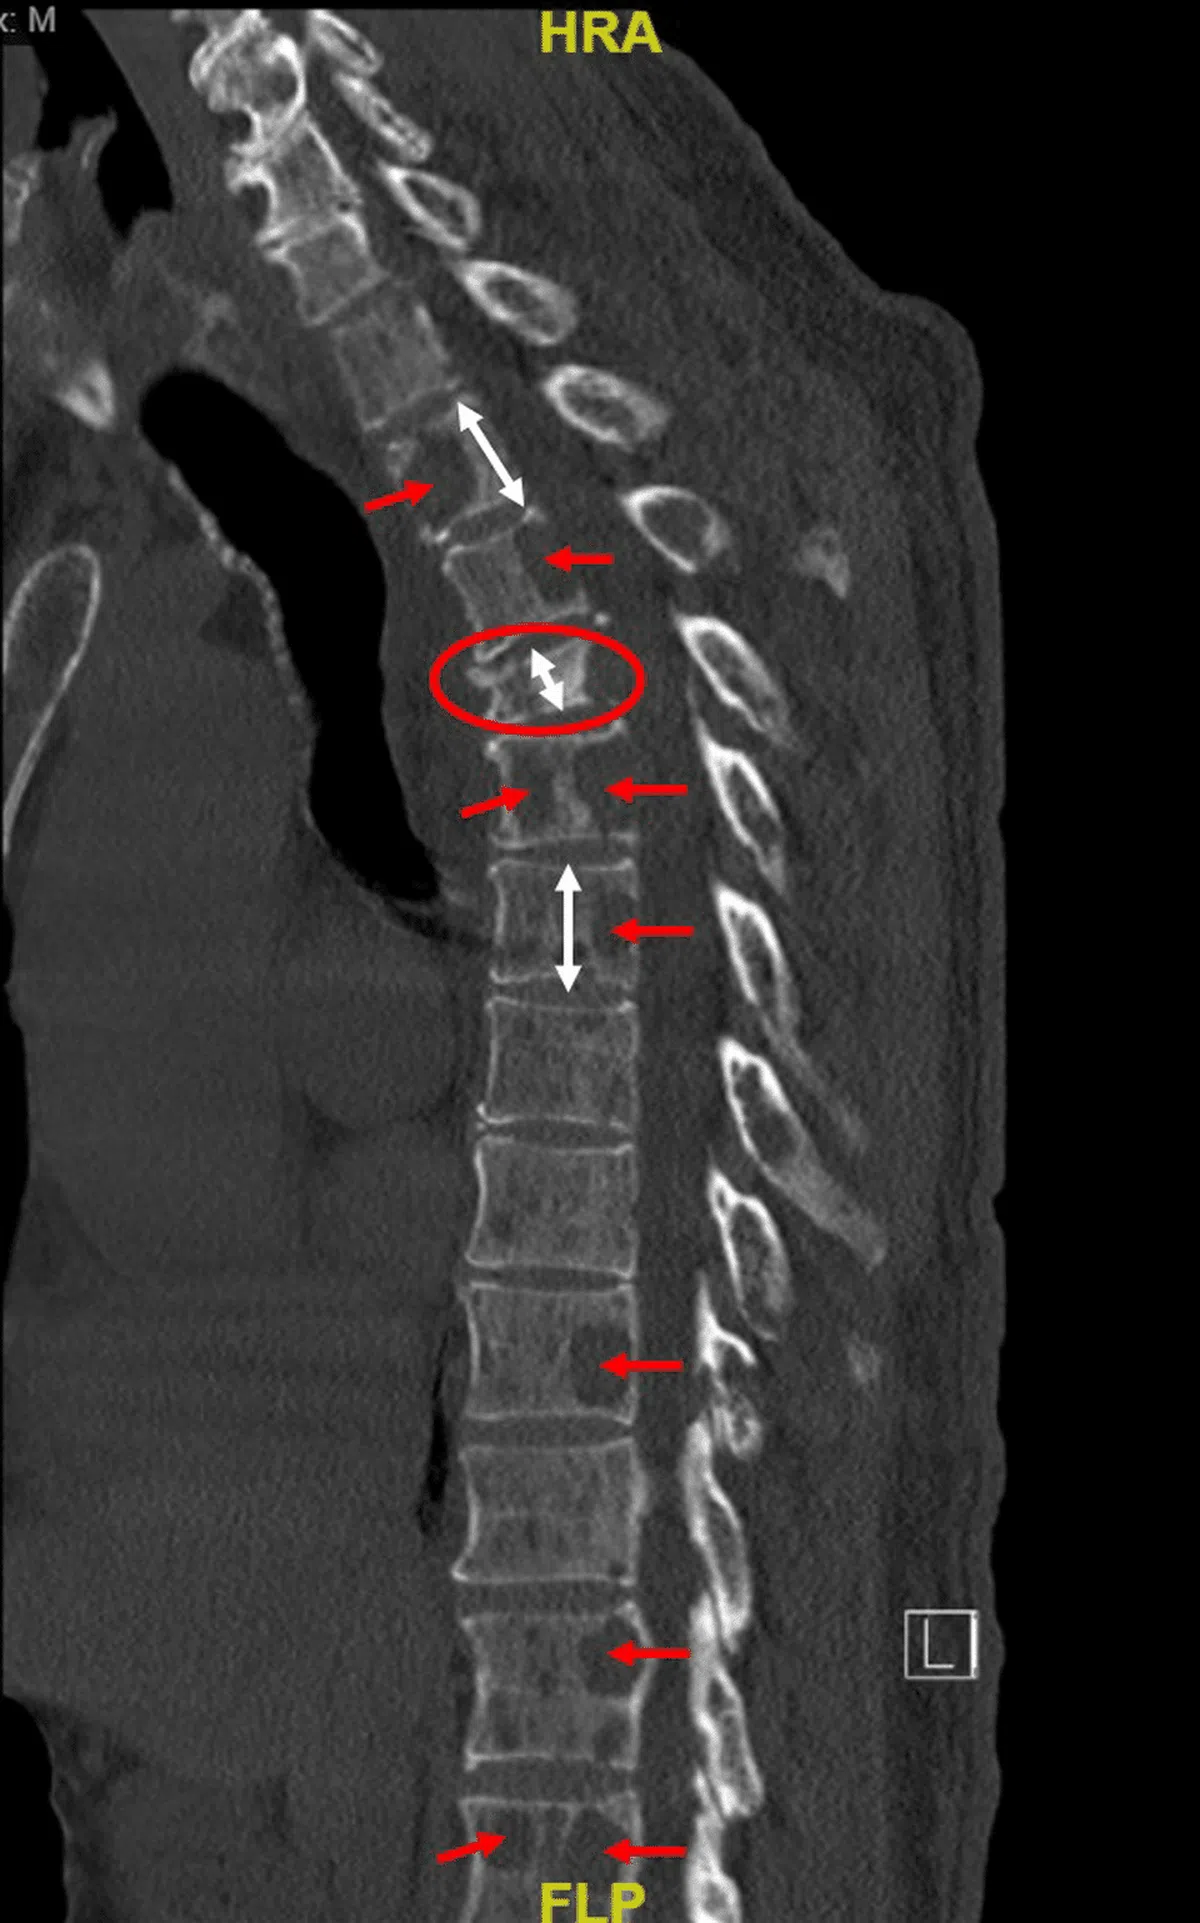

根据律师,王明星的脊椎已被癌细胞侵蚀,脊椎的结构已严重空洞化(frightening hollowing out of his spinal vertebrae)变得极度脆弱,主治医生不得已为他植入了金属支架以支撑他的脊椎。他也引用医生的医嘱:

放射影像显示,癌细胞已将王明星的脊椎椎骨“掏空”。(海峡时报)